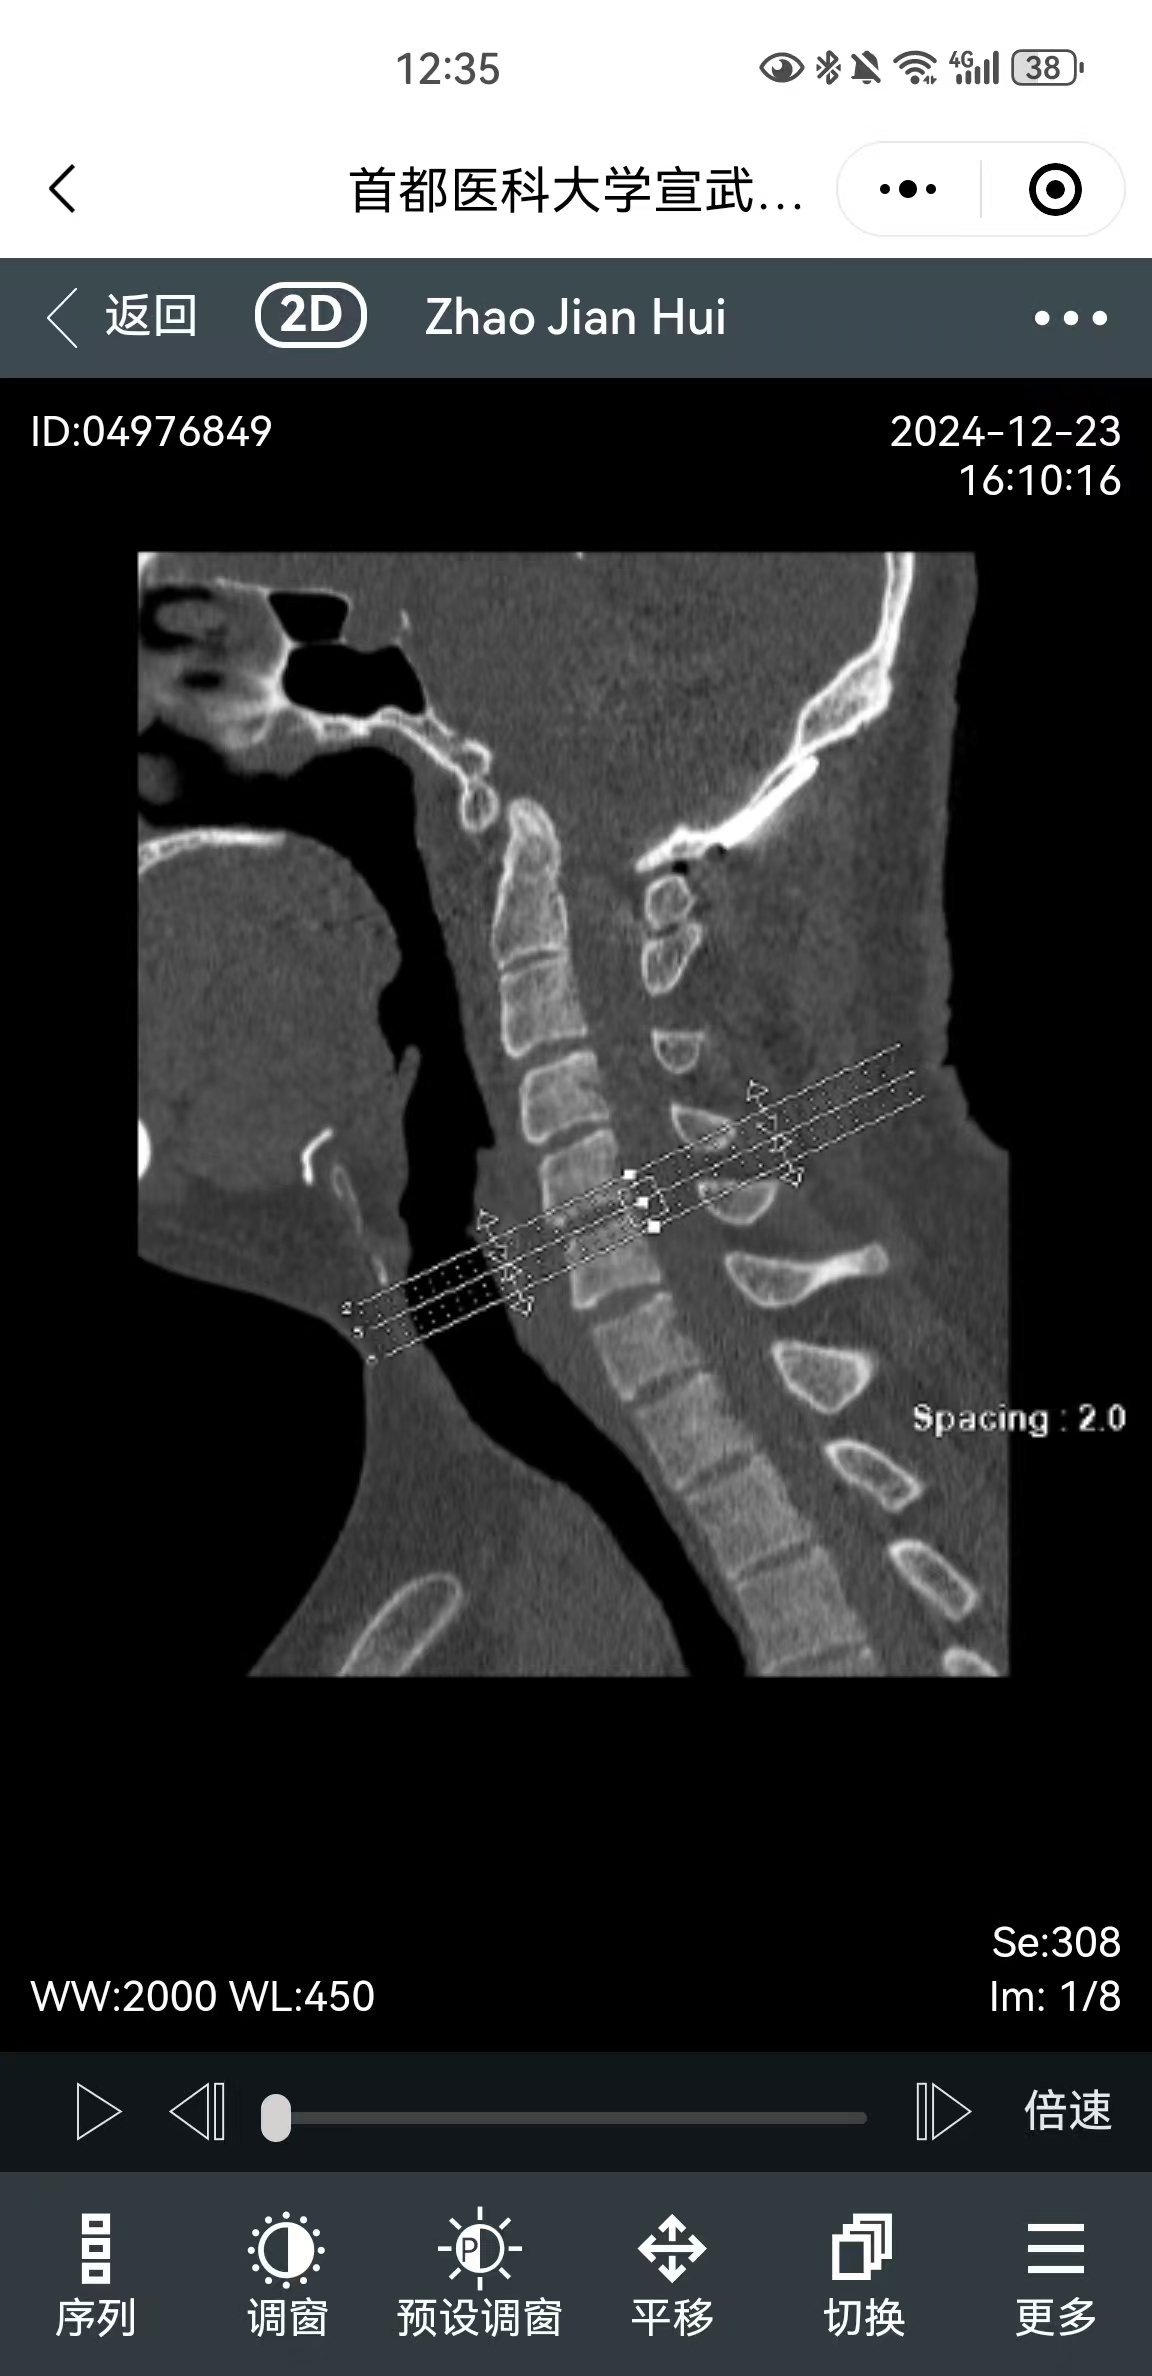

• 影像:

• 术后影像: